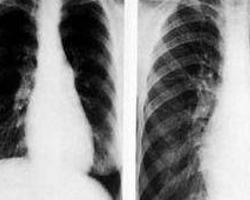

急性肺源性心脏病:来自静脉系统或右心的栓子脱落或其他异物进入肺循环,造成肺动脉主于或其分支的广泛栓塞,同时并发广泛肺细小动脉痉挛,使肺循环受阻,脉动脉压急剧升高而引起右心室扩张和右心衰竭。突然呼吸困难,胸痛、胸闷、心悸和窒息感,但可以平卧。剧烈咳嗽,或咳鲜红色血痰,数日后咳暗红色血痰。中度发热、恶心、呕吐。病情严重者昏厥、休克,甚至死亡.紫绀,呼吸频率增快.肺大块梗死区叩诊浊音,呼吸音减弱或伴有干、湿罗音。心率增快,肺动脉瓣第二心音亢进,并有收缩期和舒张早期杂音。可有心律失常。颈静脉怒张,肝肿大,有压痛,可见黄疸,双下肢水肿。